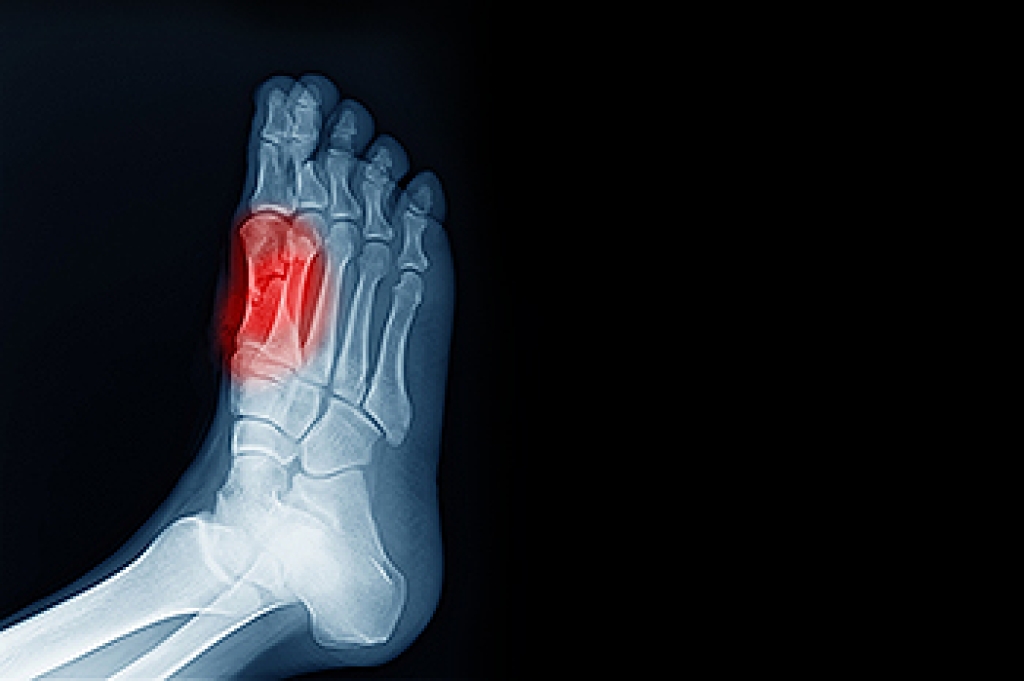

Ankle sprains take place when the ligaments in your ankle are torn or stretched beyond their limits. There are multiple ways that the ankle can become injured, including twisting or rolling over onto your ankle, putting undue stress on it, or causing trauma to the ankle itself.

Treatment of a sprain depends on the severity. Many times, people are told to rest and remain off their feet completely, while others are given an air cast. If the sprain is very severe, surgery may be required.